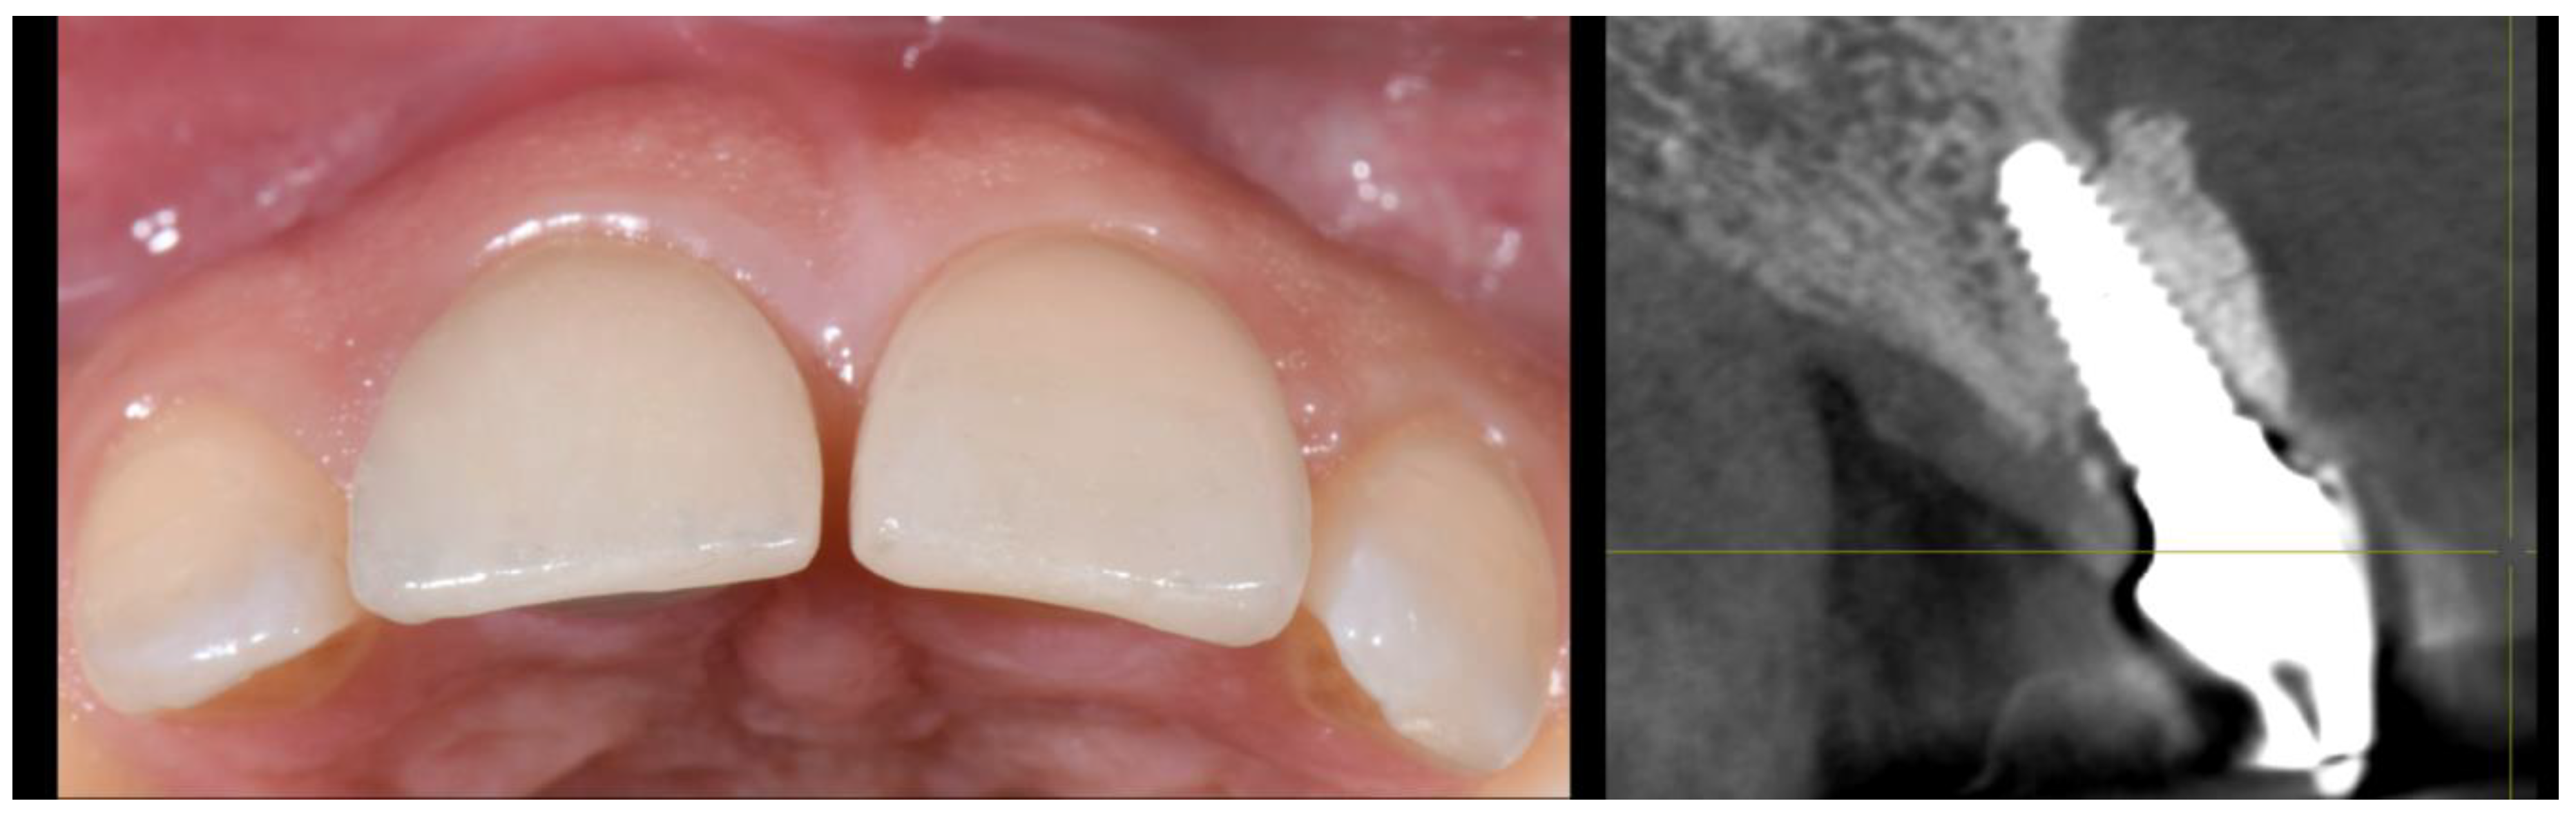

3. Case 2